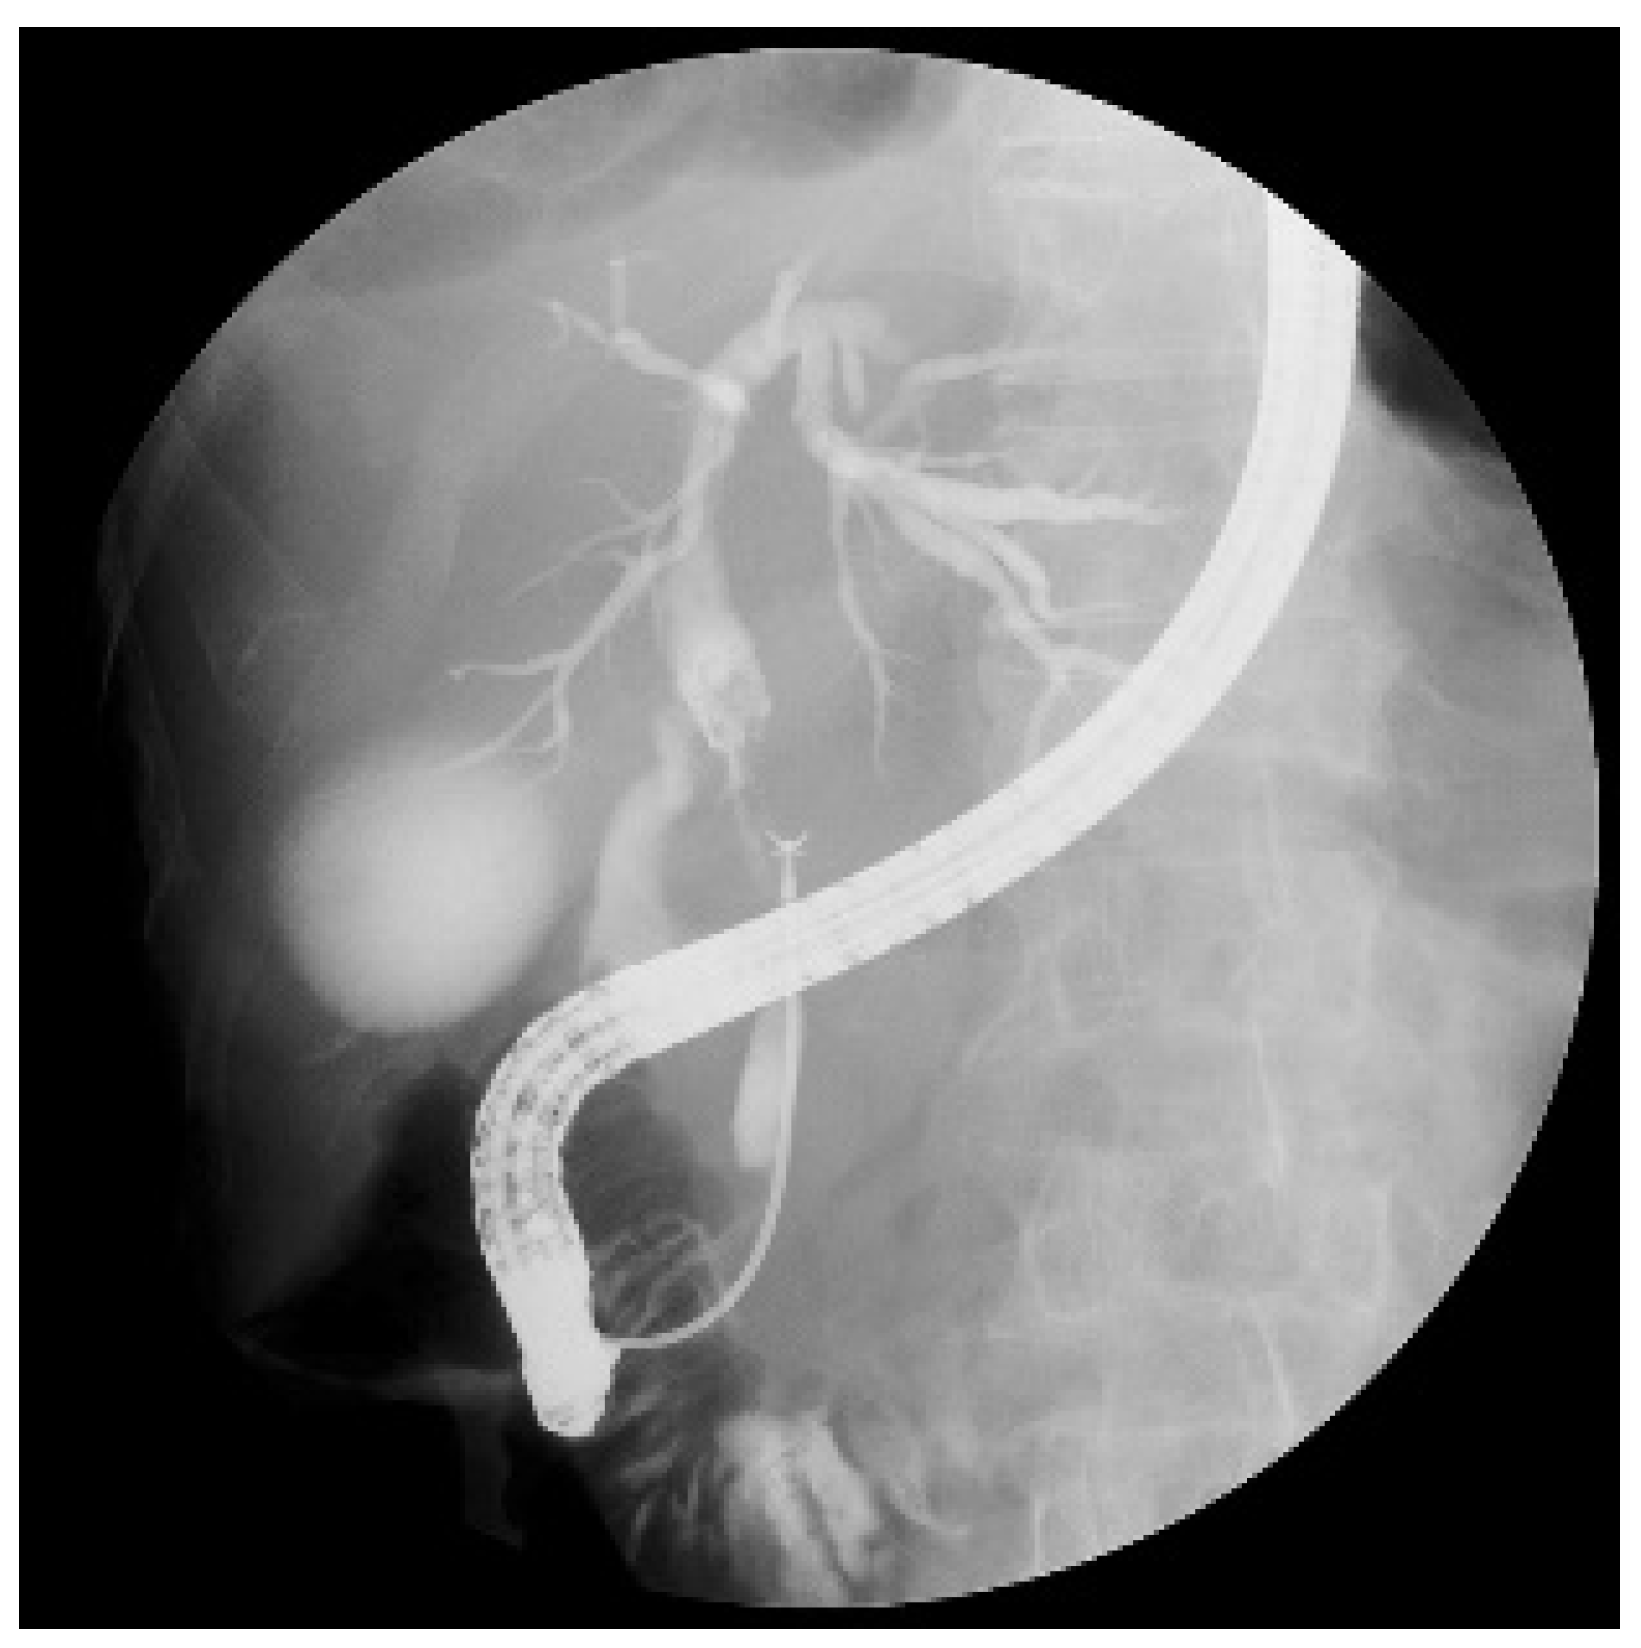

:1. Introduction

2.4. Endoscopic Procedures